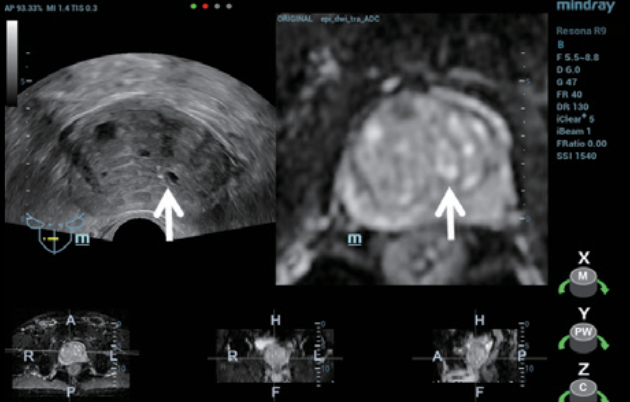

Step 1:???? MRI sequence(Figure 2) ?? ? Resona 9? ??? ??? ??? ??? ??? import ?????.

Step 2:??????? iFusion ?????? ???? TRUS/MRI ???? ?? ? ??(Figure 3) ?? ?? ???(Figure 4).

Step 3:???? ??? ???? ?? ???? ??? ?? MRI ??(Figure 5)? ???? ??? ?? ???(CEUS)? ??????.

Step 4:?TRUS/MRI ?? ??? 12 points systemic needle ????? ??? ? ???? ??? 3??? ??? ??? ?? ????? ???????.